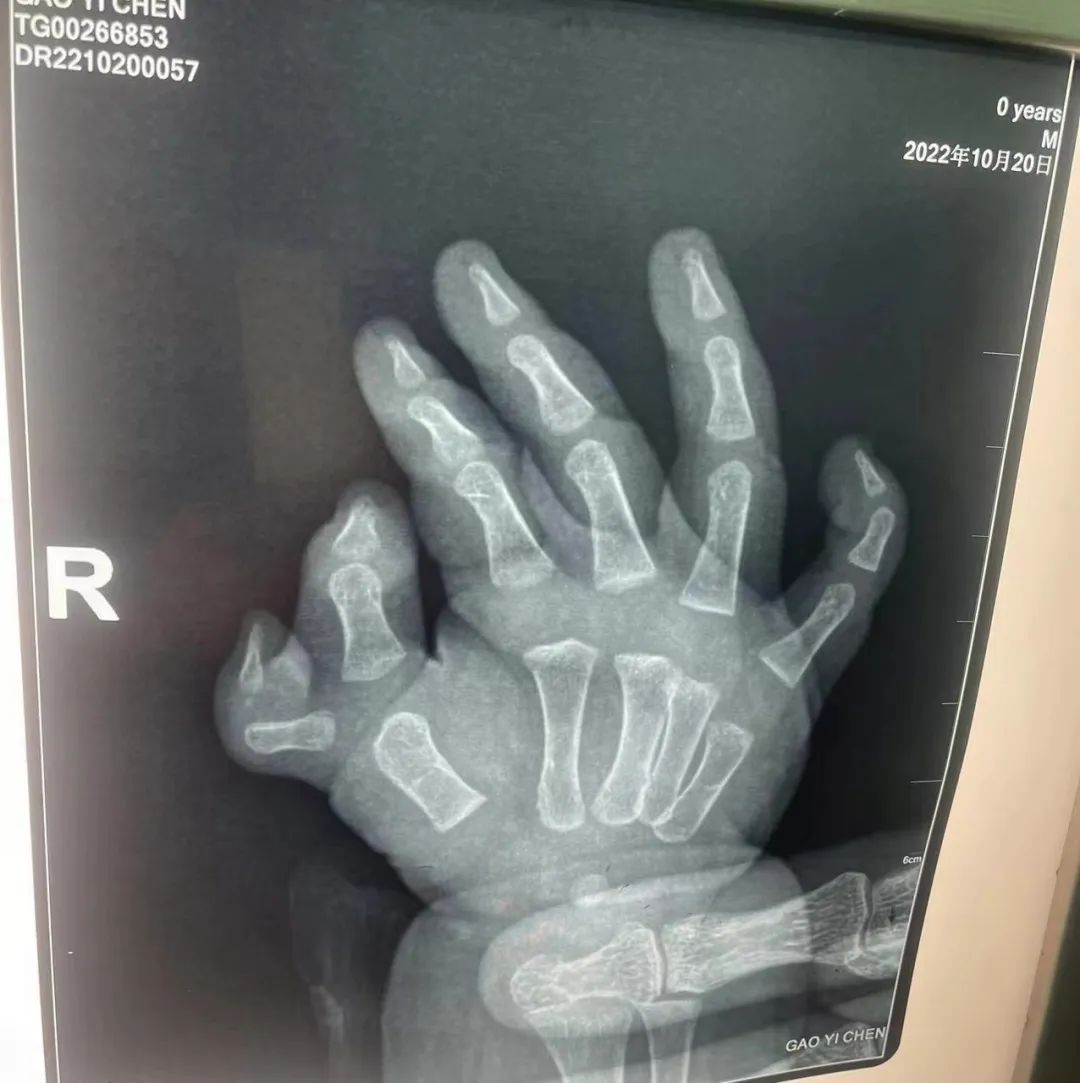

近日,我院西区手麻科就接诊一位仅有六月龄大的先天性右手六指畸形患儿。当下确保患儿术中安全及术后镇痛的问题便成了医生首要考虑的因素。面对如此超低龄患儿,麻醉医生王晓天主任医师及主诊医生邱坤副主任医师经术前慎重评估及家属同意后,决定一改往日常规气管插管全身麻醉或静脉复合全身麻醉这两种麻醉方式,而采取超声引导下肘上桡神经阻滞技术。26日上午10:35分患儿被推入手术室,得到充分镇静后,为其进行超声引导下肘上桡神经阻滞,阻滞顺利11:10手术开始,历时40分钟手术顺利结束,患儿安返病房。后经访视,患儿情况稳定。